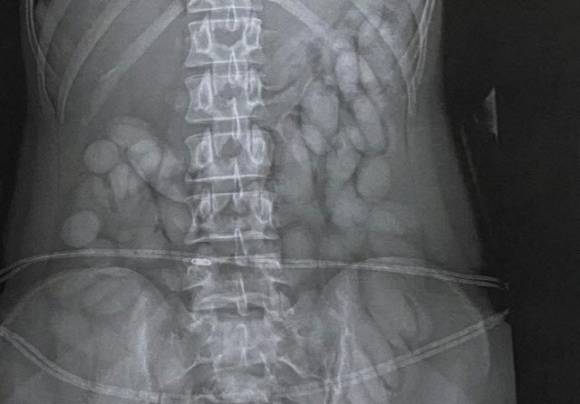

17일 방콕포스트에 따르면 오스트리아 남성 A(43)씨는 지난 11일 새벽 방콕 돈므앙 공항에서 심각한 복통과 경련 증세를 보여 인근 병원으로 이송됐다. 검사 결과 A씨의 장 내부에서 세 개의 원형 주머니가 확인됐다. 이 가운데 하나가 파열돼 심각한 내부 합병증으로 발전한 상태였다. 장 내부에는 캡슐처럼 만든 알약이 대량으로 남아 있었다.

의료진은 곧바로 수술에 들어갔고 세 개의 주머니에서 총 255정의 빨간 알약을 제거했다. 확인 결과 이 알약들은 메스암페타민(필로폰)으로 밝혀졌다. A씨는 의식을 잃은 상태였지만 경찰은 의료진의 협조를 통해 해당 알약들을 증거품으로 확보했다. 경찰은 “환자가 깨어나면 심문 뒤 사법처리할 방침”이라고 밝혔다.